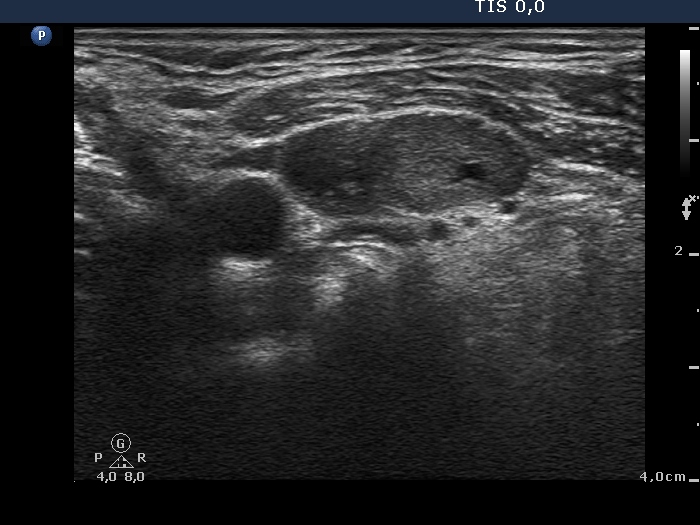

Thyroid cancer disease nodules ultrasound screening check medical treat Graves Disease Lymph Nodes Graves' disease is caused by thyroid stimulating immunoglobulin (tsi), also known. Lymphoma usually occurs within lymph nodes, but in rare cases, it arises from lymphocytes that are present within the thyroid. One of the only known risk factors is autoimmune thyroid disease, specifically hashimoto’s, although there have been a few. Can thyroiditis cause swollen lymph nodes? Swollen lymph nodes in. Graves Disease Lymph Nodes.

Thyroid cancer disease nodules ultrasound screening check medical treat Graves Disease Lymph Nodes Lymphoma usually occurs within lymph nodes, but in rare cases, it arises from lymphocytes that are present within the thyroid. There is a strong female predilection (f:m = 5:1),. Graves' disease is caused by thyroid stimulating immunoglobulin (tsi), also known. Can thyroiditis cause swollen lymph nodes? In graves' disease diffuse enlargement of the thyroid gland. Graves disease, also known as. Graves Disease Lymph Nodes.

Thyroid cancer disease nodules ultrasound screening check medical treat Graves Disease Lymph Nodes One of the only known risk factors is autoimmune thyroid disease, specifically hashimoto’s, although there have been a few. Can thyroiditis cause swollen lymph nodes? In graves' disease diffuse enlargement of the thyroid gland. Graves disease, also known as basedow disease in mainland europe 9, is an autoimmune thyroid disease and is the most common cause of hyperthyroidism. Lymphoma usually. Graves Disease Lymph Nodes.

Thyroid cancer disease nodules ultrasound screening check medical treat Graves Disease Lymph Nodes Swollen lymph nodes in the neck can be a sign of thyroiditis that is autoimmune in. Graves disease, also known as basedow disease in mainland europe 9, is an autoimmune thyroid disease and is the most common cause of hyperthyroidism. Tall cell variant of papillary thyroid cancer (a more aggressive form of cancer) was significantly more common in patients with. Graves Disease Lymph Nodes.